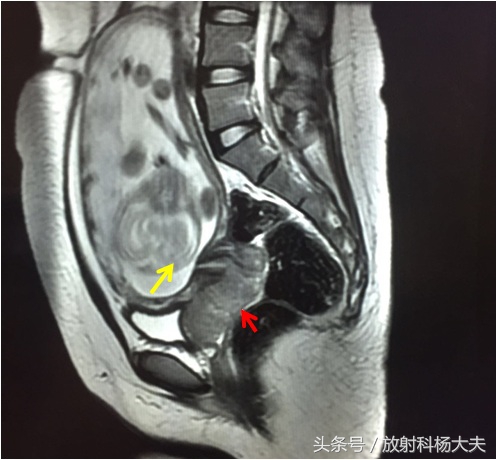

两年前遇到一个病例,女性,23岁,孕20周+4天,因阴道流血来医院检查,小两口很紧张,以为是孩子出了什么问题,做了超声,结果是宫颈占位,所以临床大夫又给患者开了核磁申请单,大家可能会想,不是超声已经确诊是宫颈占位了么,为什么还要做核磁(MRI)。针对宫颈病变,MRI可以说是最好的检查方法,可以直接的视察肿瘤的大小,视察阴道及宫旁侵犯,视察盆腔内淋巴结及对病变进行分期。先给大家上图:

红箭所指的地方就是病变,还可以看见肚子里的宝宝(黄箭)。而且经过进一步的分析,病变已经累及阴道及直肠,提示为宫颈癌的晚期!

针对局部病变的显示,MRI无疑是最好的。因此临床上进行术前分期的时候都选择MRI检查。宫颈基质的低信号环是否完整是宫颈癌I期与II期的分界标志,完整的低信号环说明癌灶局限在宫颈,可排除有宫旁组织的侵犯。如低信号的基质环被高信号的肿瘤破坏,出现中断或是突破,提示肿瘤已经侵犯宫旁组织,属于II期。肿瘤累及阴道下1/3、盆腔、直肠等周围脏器,为III 、IV期。